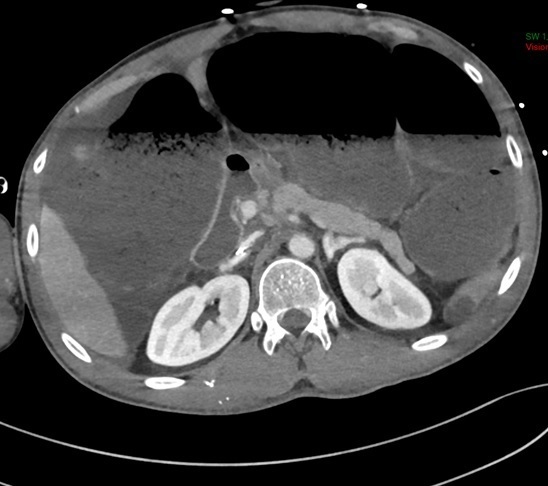

Un scanner cérébral est réalisé

Question 6 : Parmi les propositions suivantes, laquelle (lesquelles) est (sont) exacte(s) ?

Difficile à voir au scanner, c’est l’imagerie par résonance magnétique (IRM) qui permettra le mieux d’apprécier la présence de plaques

Aucune hyperdensité spontanée n’est visible

Même si les ventricules latéraux paraissent légèrement élargis, les sillons corticaux sont eux-mêmes larges et il s’agit donc plutôt d’une atrophie cortico-sous-corticale modérée

Le scanner cérébral peut être considéré comme normal, en dehors d’une atrophie cortico-sous-corticale modérée.